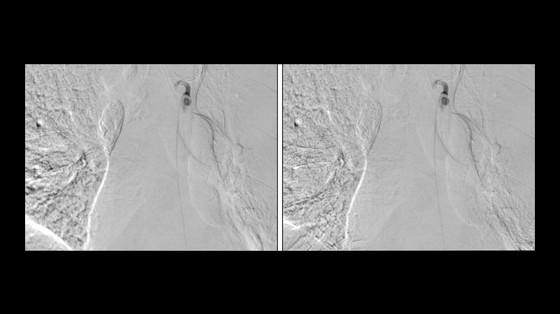

曾经,国内95%以上的DSA市场被国际巨头垄断,三级医院难觅国产设备踪影。如今,这一格局已被打破——东软医疗自主研发的高端DSA产品,不仅实现了国产突围,更已服务全球超过15万名患者。 2025年上半年数据显示,国产DSA已占据国内18%的市场份额,其中近一半(8.1%)属于东软医疗,成为形成有效影响力的国产品牌。 01 打破垄断, 国产DSA的崛起之路 DSA(数字减影血管造影机)是介入诊疗的核心设备,被誉为“介入医生的眼睛”。其研发涉及医学影像学、机械学、电子学等十余门学科,技术壁垒极高。 2016年,东软医疗正式启动DSA研发项目,代号“贝加尔湖”。 2017年,公司以排名第一的成绩承担国家“低剂量数字减影血管造影(DSA)研制”重点研发计划。 2019年,东软医疗推出中国首款无轨悬吊七轴智能DSA——NeuAngio 30C“汉武”,填补了国产高端DSA空白。随后又相继推出NeuAngio 30F“汉·光武”落地式DSA和NeuAngio-CT“汉·文景”一站式诊疗解决方案。 经过多年发展,东软医疗DSA已实现全球500台装机(国内450台,海外50台),其中40%以上为三甲医院,复购率超30%,稳居国产DSA品牌首位。 02 技术领先, 四大王牌构建产品矩阵 东软医疗DSA能从高度垄断的市场中突围,依靠的是其四大王牌产品与技术: ▍王牌一:高端DSA设备 东软医疗全球首创的双旋转中心结合七轴机架设计,使机架纵向可移动范围达到2.3米,横向可实现2.74米的移动,无需轨道就可以灵活摆位,满足从头到脚的大覆盖范围,为简化介入手术工作流程和缩短操作时间提供了有力保障。 自2022年起,东软DSA已连续4年独占国产DSA市场一半的市场份额,并向GPS发起冲击。在这样的背景下,2025年东软DSA的同比增长率仍高达50%,也充分说明了两件事:国产DSA市场需求旺盛,将长期欣欣相容;东软DSA的临床使用体验已获得医生们的认可和推荐,多家医院2-3台的复购,便是很好的证明。 ▍王牌二:Angio-CT一站式解决方案 在我国,Angio-CT主要装机于三级医院,市场需求量约30-50套/年,为GPS垄断。东软医疗Angio-CT的出现,不仅填补了国内空白,也占领了近50%的国内市场份额。成功的这背后,靠的正是其差异化优势。 相较于进口品牌大多使用64层以下CT,东软医疗NeuAngio-CT是业界唯一一款可配置512层高端滑轨CT+DSA一站式解决方案,结合其一站式胸痛三联征解决方案、一站式脑卒中解决方案,对于三大中心建设更具优势。 比如,NeuAngio-CT多影像一站式急诊卒中解决方案、急诊胸痛解决方案、急诊创伤解决方案,将急诊影像检查与介入手术进行有效联合,不仅避免转运过程中带来的时间贻误、感染、生命体征不稳定等医疗风险,还能协助术前规划、术中引导、术后评估,大幅提高介入手术的治愈率。 东软医疗NeuAngio-CT在吉林大学中日联谊医院使用 ▍王牌三:复合手术室+机器人 以往,大家的传统观念是,由于复合手术室中需要DSA与外科手术床联动,在这方面国产DSA无法满足,这么大这么重要的市场没有国产怎么行? 如今,不再是,东软DSA已实现与Trumpf手术床的完美联动,是国内唯一实现与手术床联动的国产DSA,可根据治疗需求一键自动切换外科手术-实时成像-介入手术等状态,让临床实现“该做手术时做手术,该做介入时做介入”的理想复合手术室状态,满足各种复杂临床应用场景。 东软医疗DSA与Trumpf手术床完美联动 目前,东软复合手术室已在等南方医科大学珠江医院等近10家医院装机。未来,随着其的临床使用体验愈发被认可,随着其DSA+CT、甚至DSA+CT+MR等多模态复合手术室的推出,将有助于其获得更大的市场份额。 此外,东软医疗与美国Stereotaxis公司战略合作, 推出了DSA+机器人解决方案,将落地式DSA——NeuAngio 30F与磁导航心脏消融机器人无缝匹配,开创了心导管射频消融术(RFCA)精准治疗新时代。 东软医疗DSA和磁导航机器人融合 ▍王牌四:HAN-Link“智”平台 东软HAN-Link平台依托依托IDM 2.0智控中枢,量子-态坍缩智能降噪技术、冠脉 HD4.0、神经 HD4.0等先进技术,在各临床场景下均能输出高清影像,空间分辨率提高62%,辐射剂量降低73%,造影剂用量减少58%;此外,配合独呼吸伪影抑制技术,有效解决呼吸干扰问题,提升影像可靠性的同时减轻患者负担,实现高清、低剂量、自然成像的介入新标准。 应用量子DSA前(左)和应用量子DSA后(右) HAN-Link所带来的影响,远不止于图像质量的提升与辐射剂量的降低。还以人工智能赋能介入诊疗全流程,构建医生、患者、设备间的智能交互体系。通过 AI 辅助功能如血管全循环彩色影像、肿瘤栓塞导航、CTO 导航、TAVR 导航等,提升手术精准度与效率。 此外,智能语音助手、卓影灌注分析、免定标测量、低剂量实时多角度DSA采集、多期卓影CT、穿刺定位导航、实时支架精显等一系列高级应用,为介入医学领域提供了更智能、更安全、更贴心的解决方案。 HAN-Link平台的手术实时指导规划系统 比如,在心脏介入领域中的实时支架精显,可协助医生在放置球囊、支架和BVS耗材时,快速验证定位,实时显示未充分释放的支架,并确认支架是否完全展开及贴壁情况。在常规血管狭窄和支架内再狭窄的支架植入术、分叉病变的多支架植入术和支架断裂后支架桥接治疗等术式中有着重要意义。 03 临床认可, 从怀疑到信赖的转变 东软医疗DSA凭借不输进口品牌的卓越表现,赢得了临床专家的广泛认可。 中国医科大学附属第一医院徐克教授指出:“DSA设备长期被欧美品牌垄断,东软医疗作为国产领军企业,率先推出国产高端DSA,树立行业标杆”。 中国人民解放军总医院第八医学中心敖国昆教授评价道:“NeuAngio 30C‘汉武’DSA的整体质量达到了国际先进水平,其首创的无轨悬吊双旋转中心结构,为被动体位的患者治疗带来了诸多便利”。 东南大学附属中大医院张毅教授分享了对国产DSA从怀疑到信赖的转变过程,肯定东软医疗DSA的软件后处理能力和CBCT技术在出血检测、支架形态判断等方面的价值。 04 全球布局, 从中国走向世界 东软医疗DSA不仅在国内市场表现出色,还成功打入国际市场。 2024年,东软医疗成功在意大利、英国、德国、葡萄牙等国家实现销售,在“一带一路”沿线的南美、拉美地区以及中亚独联体国家获得广泛认可。 2025年第一季度,东软医疗国际合同订单涨幅远超预期。公司计划进一步拓展非洲、东南亚、中东市场,持续扩大全球业务影响力。 目前,东软医疗在中国DSA市场中稳居第四位,与GE医疗、飞利浦、西门子医疗三大外资巨头形成“3+1”竞争态势。 05结 语 从2016年地下车库起步,到如今产品进驻国内40%的三甲医院;从首台设备获批上市,到全球500台装机。 东软医疗DSA的十年征程,印证了中国高端医疗装备从“跟跑”到“并跑”乃至“领跑”的蜕变。 今天,东软DSA以“技术突围”为笔,以“临床需求”为墨,在国产高端医疗设备领域书写着创新篇章;未来,东软DSA一定会越来越好,成为中国智造在全球高端介入诊疗的新标杆。